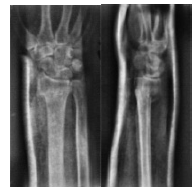

ճաճաևչոսկրի դիստալ Մետաէպիֆիզի տեղաշարժված կոտրվածք

Կոևտրոլ`դիաֆիքսացիայից հետո